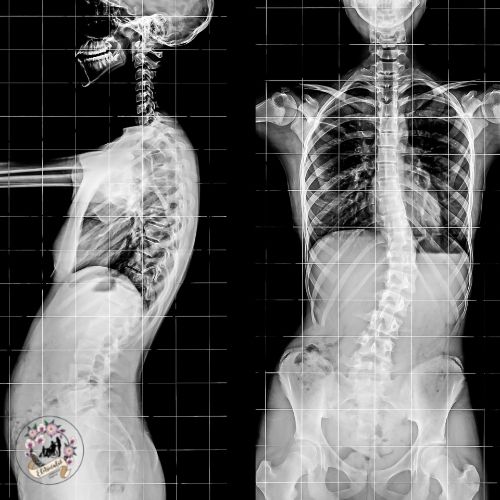

gerincferdülés esetén

porckorongsérv, gerincferdülés, Scheuermann